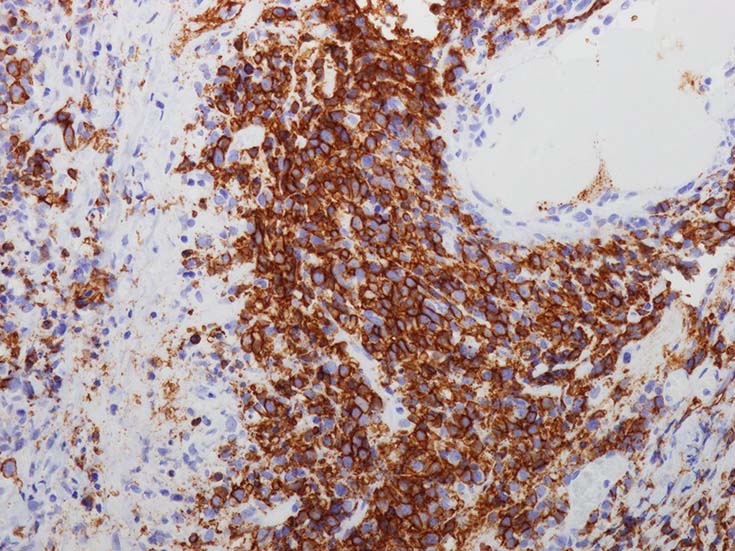

腫瘍細胞はCD20+. CD30の顕著な発現は共通の特徴であるが,CD15の共発現は見られない.

バックグラウンドの浸潤細胞は,小型のT細胞(CD3+,CD4+>CD8+)で構成されている.B細胞はEBER陽性で, EBNA2(+/-); EBV潜伏タイプIIIを示すが, IIの場合も少なくない. (III>II)

EBER-ISH染色は病変のGradeや血管侵襲の程度にもよるが, 陽性B細胞は大小さまざまで不均一である.

免疫染色

血管中心性浸潤. 障害された血管内に血栓が形成されている.CD20陽性細胞がシート状密に浸潤, CD3陽性T細胞が多く混在している. EBER-ISH陽性 EBV感染細胞が多数認められ, >50 hpf, 定義より Grade3となる. 陽性細胞のサイズは大小さまざまであることに注意. Lymphomatoid granulomatosisの病態(WHO5thの診断では EBV-positive diffuse large B-cell lymphomaになる)をとっているが MTX-associated LPDの一型とするべき症例かもしれません.